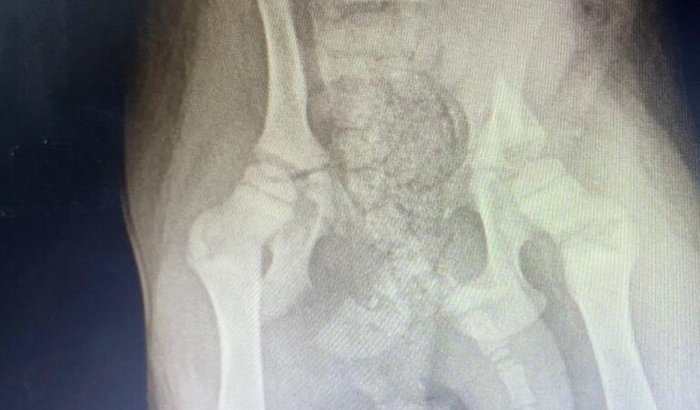

Oi me chamo oncio Nessa madrugada do dia 21/04/25Uma cadelinha de no máximo 3 meses foi atropelada custeei metade do tratamento q ficou em torno de 4 mil no veterinário mais em conta conto com sua ajuda  ver tudo

Nessa madrugada do dia 21/04/25

Uma cadelinha de no máximo 3 meses foi atropelada custeei metade do tratamento q ficou em torno de 4 mil no veterinário mais em conta conto com sua ajuda